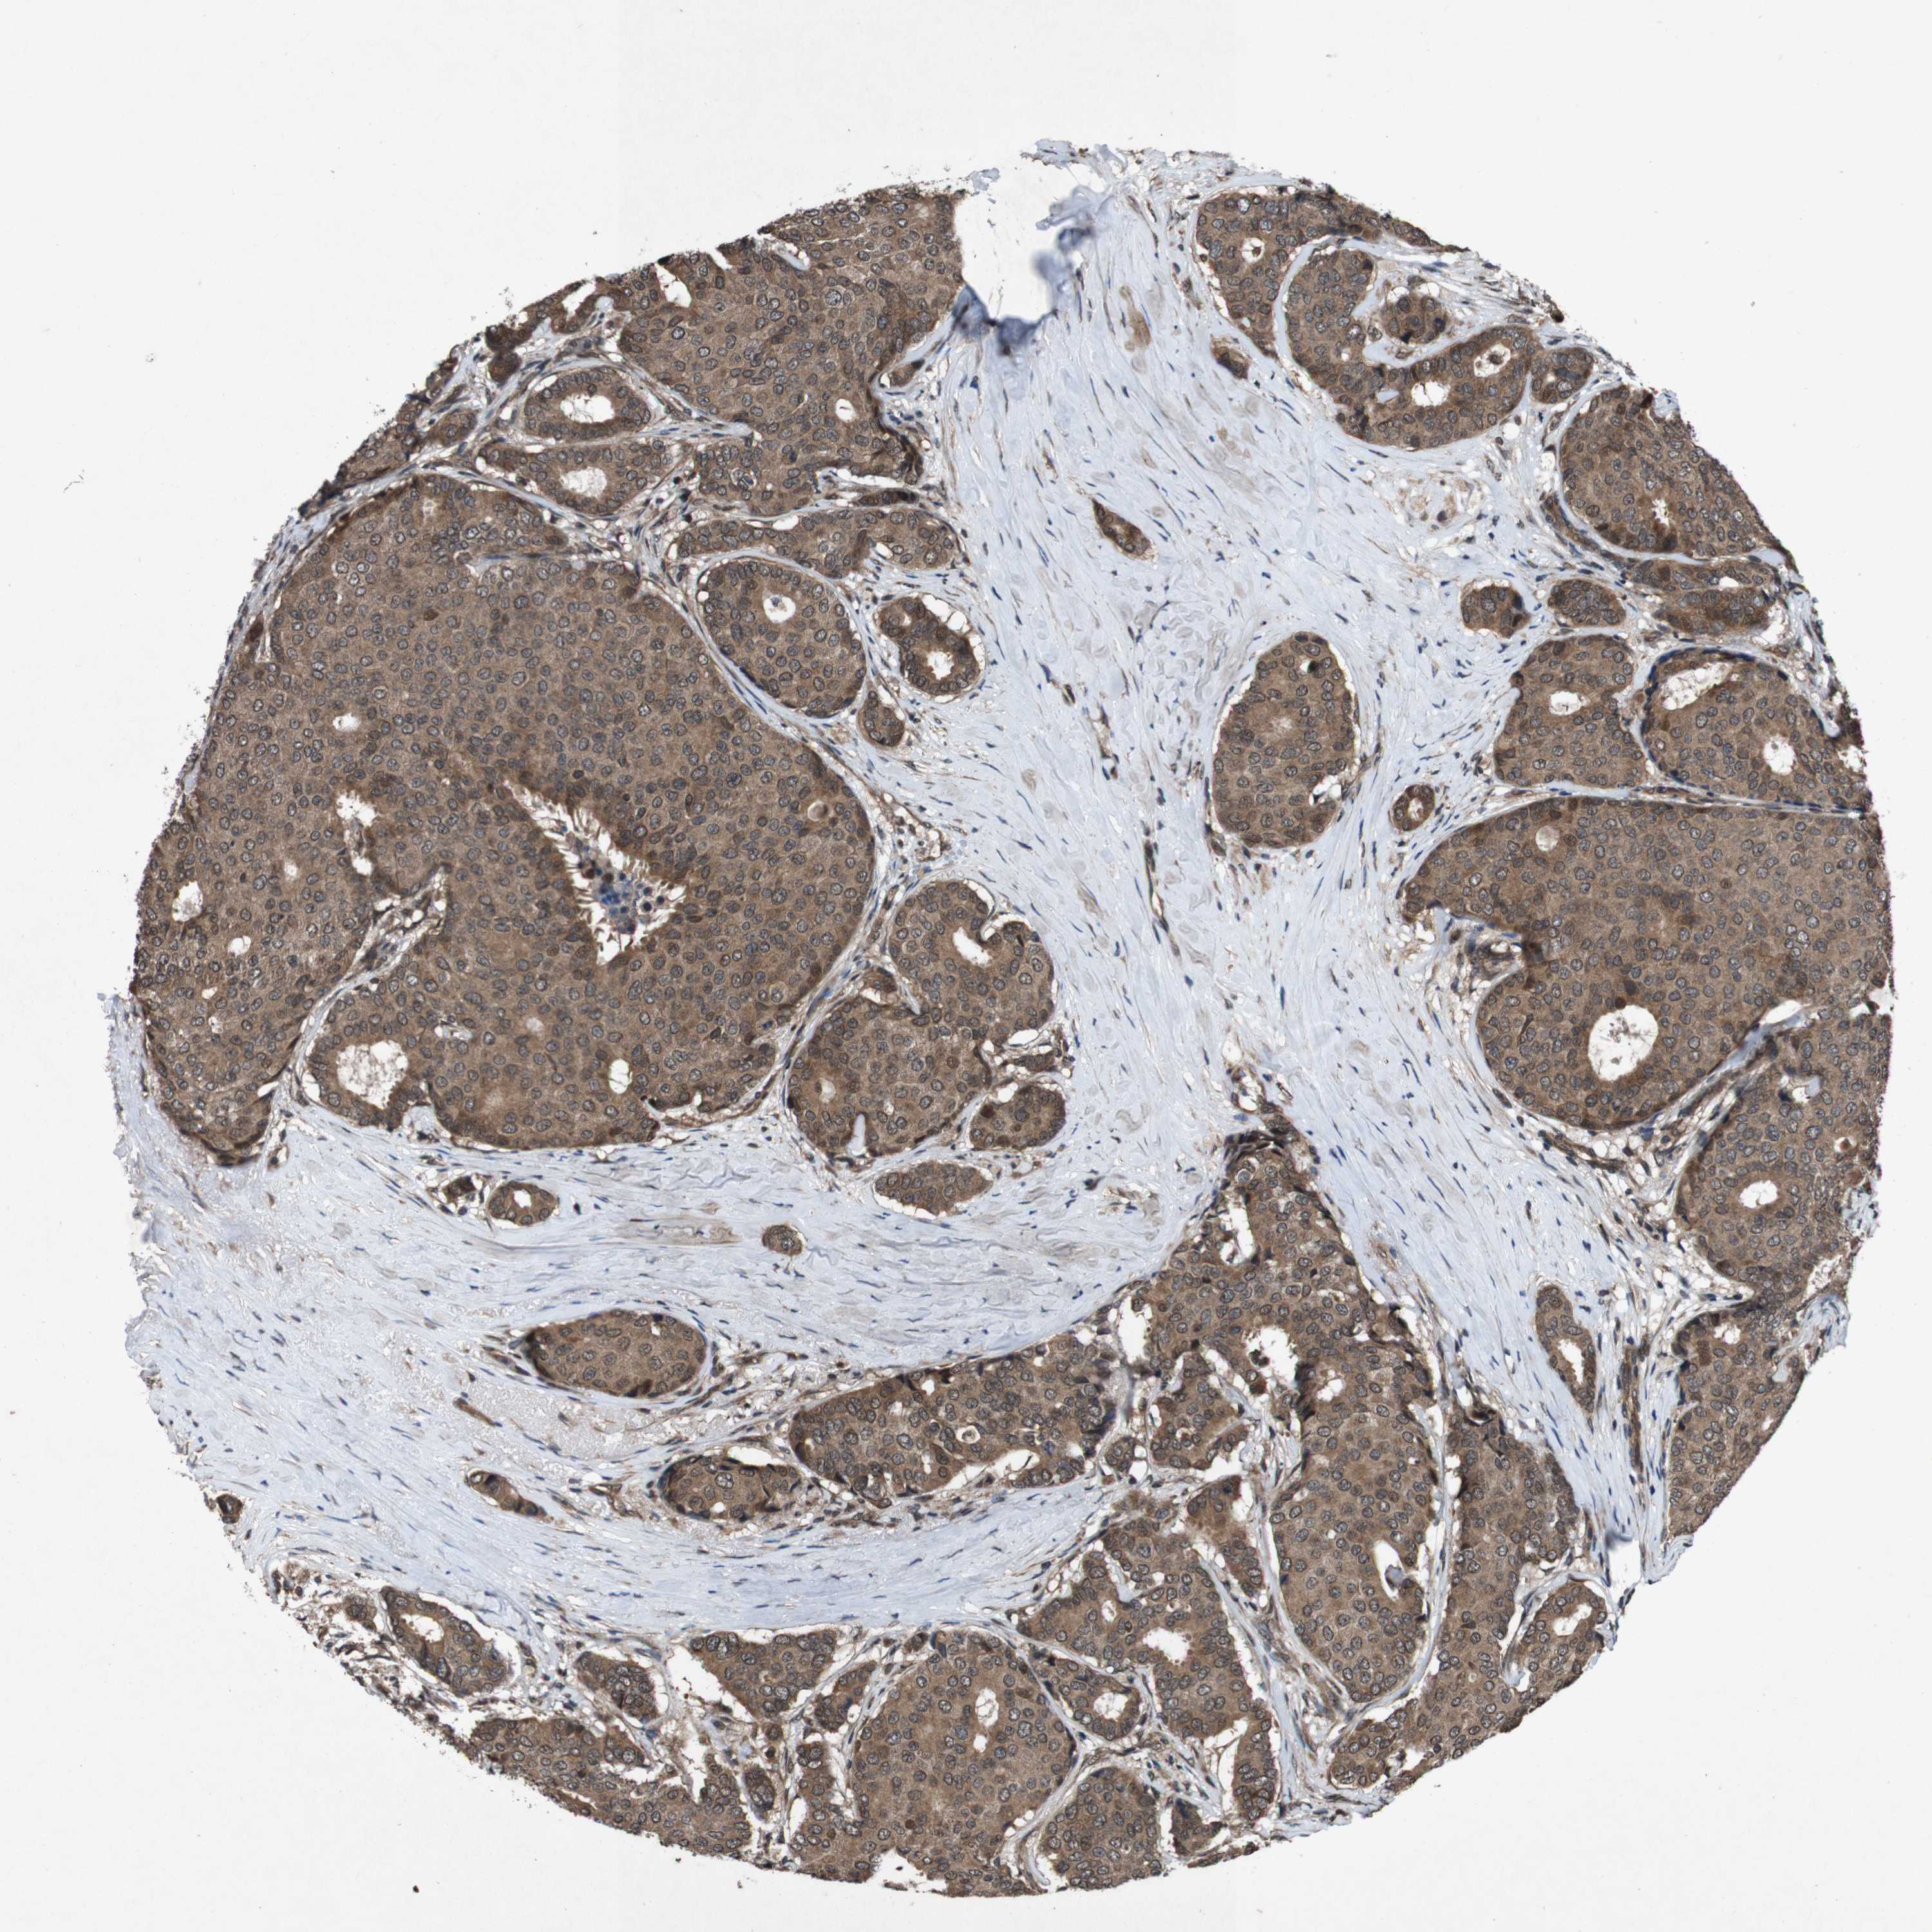

BRCA TCGA BRCA VALIDATION PROTEIN EXPRESSION

ANTIBODIES

AND

VALIDATION